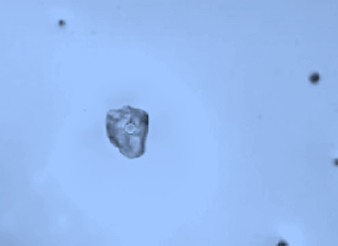

정말 일회용 점안제 안에 용기의 파편이 존재하는지 광학 현미경을 통해 관찰한 결과 파편이 발견되었다.

그 크기는 대부분 마이크로 사이즈로 확인되었으며 30~40 마이크로미터의 사이즈를 가지고 있었다.

일회용 점안제(인공눈물)의 용기 성분은 저밀도 폴리에틸렌(Low Density Polyethylene) 성분으로 만들어지는데 발견된 미세 플라스틱의 성분 또한 일치했다.